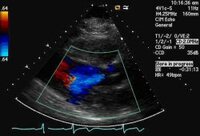

Parasternal long-axis view demonstrating aortic regurgitation jet width and height

From the collections of Dr Sanjeev Wasson and Dr Nishant Kalra; used with permission